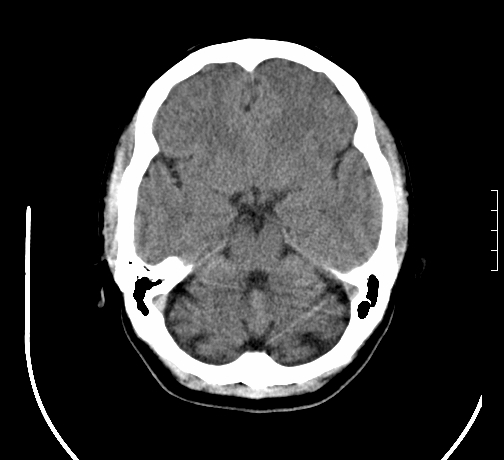

女,28岁,幼时有癫痫,常有发作,服药后可几月不发作,走路不稳3-4月,加重一月。

小脑发育畸形?

小脑萎缩。

考虑小脑发育不良,建议mri检查。

患者出现走路不稳是近几个月的事,而癫痫则有幼时就有,常发,则会常服药,癫痫药可引起小脑综合症,小脑萎缩,而小脑发育不良的主要症状不是癫痫

考虑癫痫,长期间断发服抗癫药,导致小脑综合症,小脑萎缩

考虑小脑发育不良伴小脑萎缩,建议mri检查。

小脑萎缩,原因待查,建议mri检查。

考虑小脑发育不良伴小脑萎缩,建议mri检查

考虑药物性小脑萎缩